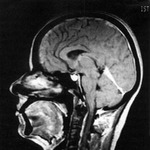

Visszanőtt a koponyacsontja feje tetején egy brit férfinak.

Fél évszázaddal ezelőtt autóbalesetben sérült meg annyira, hogy fémlemezzel kellett pótolni fejtetőjét. A koponya az egyetlen csont, mely nem forr össze, és bár nő, illetve szélesedik valamelyest, fél fejnyit nem. Ezért is hűltek el az orvosok, amikor szembesültek azzal, hogy az immár 72 éves férfi hiánytalan koponyatetőt "növesztett" magának – adta hírül a Daily Telegraph című brit lap.

A férfi azért került kórházba, mert a fémlemez miatt fertőzést kapott, és annak kezelése miatt az orvosok úgy döntöttek, le kell venni a titánlapot. Alatta azonban nem az agyhártyára bukkantak, hanem koponyára. Végül csak össze kellett ölteniük a lemez levétele miatt vágásoknál a bőrt, nem volt szükség új fémfejtető-protézisre, amelyre egyébként hónapokat várt a férfi. Immár "hajadonfővel" élhet.